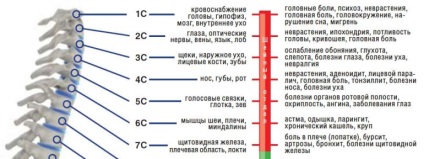

Ezen kívül, úgy gondoljuk, hogy összefüggés van a között bizonyos lemezek elváltozás a gerincoszlop és a belső betegségek (lásd. A rendszer az alábbiakban).